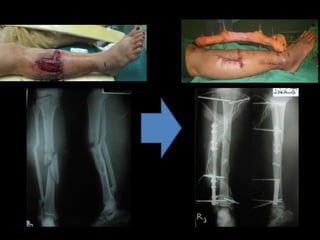

Type~III Open Fracture of the Fore Arm

III

A Usually

>10 cm

long

High Severe with crushing Usually comminuted;

soft tissue coverage of

bone possible

B Usually

High Very severe loss of coverage;

usually requires soft tissue

reconstructive surgery

Bone coverage poor;

variable, may be

moderate to severe

comminution

Type~IIIC Open Fracture of Femur

IIIC Usually

High Very severe loss of coverage

plus vascular injury requiring

repair; may require soft tissue

Fracture stabilization

(internal or external fixation)

• provides protection from

additional soft tissue injury,

• maximum access for wound

management,

• maximum limb and patient

mobilization